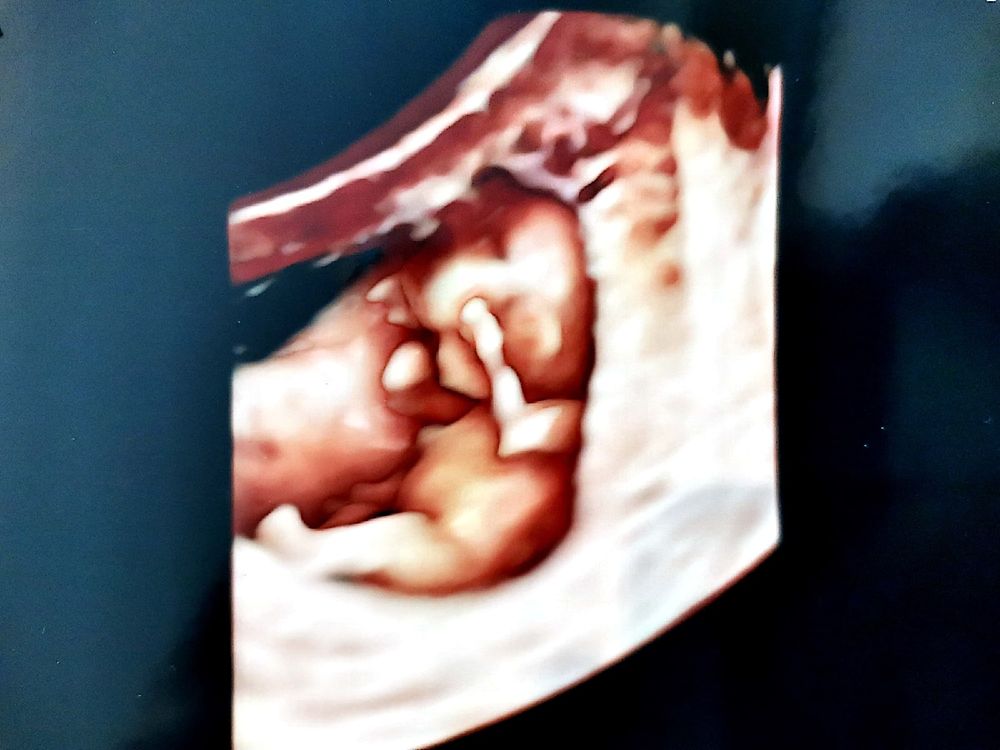

А вот и УЗИ😌:

Всмысле нарушение кровотока правой маточной артерии... Что ни УЗИ, то новые приколы. Зато ПОЛНОЕ предлежание испарилось, это как🤔? Плацента могла подняться за 3 недели? Если да, то я счастливый как никто 😄😌